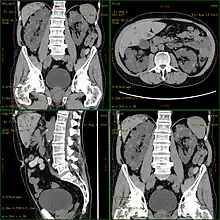

![]() | |